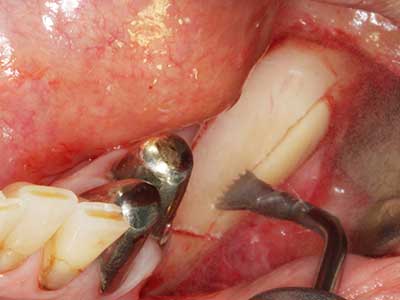

Indication: Preparation near nerves

As noted above, indications for piezosurgery can also be found in the field of conservative dental surgery. Special working tips simplify the exposure of root tips and make it easier to protect nerves and sinus mucous membranes, particularly in the lower premolar and upper posterior tooth regions. Angled diamond tips are used to precisely prepare the resection cavity for the retrograde root filler material for unsealed apical obturation. The ultrasonic technology means the tips can be very slender, which improves the view and the size of the access cavity. As a result, the application of ultrasonic surgery for this indication is one of the standard procedures for apical resection (Del Fabbro, Tsesis et al. 2010, Scarano, Artese et al. 2012).

Indication: Apical resection

When surgical procedures are performed on bone in the immediate vicinity of sensitive structures such as blood vessels or nerves, rotary instruments pose a significant risk of iatrogenic injury. Piezoelectric devices can be helpful for preparation of bone covers and removal of hard tissue close to nerves, particularly for exposure of nerves after iatrogenic injury but also during nerve lateralization for resective and reconstructive procedures or implant placement (Fig. 17-20). Light contact between the piezotip and the nerve does not generally result in damage but proceeding incautiously with saw-like motions or attachments where a residual bone substrate remains may cause temporary or even permanent nerve damage. However, the risk of damage is considered to be substantially lower than when using saws or milling instruments (Pereira, Gealh et al. 2014).